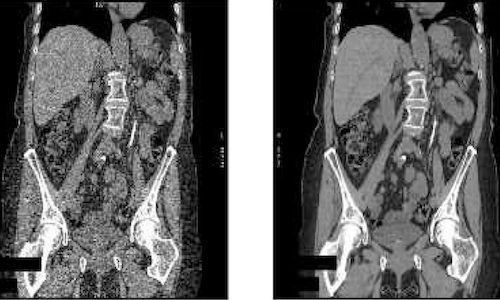

New technology allows CT scans to be done with a fraction of the conventional radiation dose

“We’re excited to be adding Veo to the measures we already have in place to ensure that we get diagnostic images using the lowest amount of radiation possible.”

Fighting lung cancer: Faster image processing for low-radiation CT scans

This advance could be important for fighting lung cancers, as symptoms often appear too late for effective treatment.

Using data science to achieve ultra-low dose CT image reconstruction

Ultra-low dose CT scans that provide superior image quality could not only benefit patients, but they could open up entirely new clinical applications.

Students win prizes for improving image processing techniques for liver cancer detection and much more

Students in EECS 556: Image Processing, explore methods to improve image processing in applications such as biomedical imaging and video and image compression